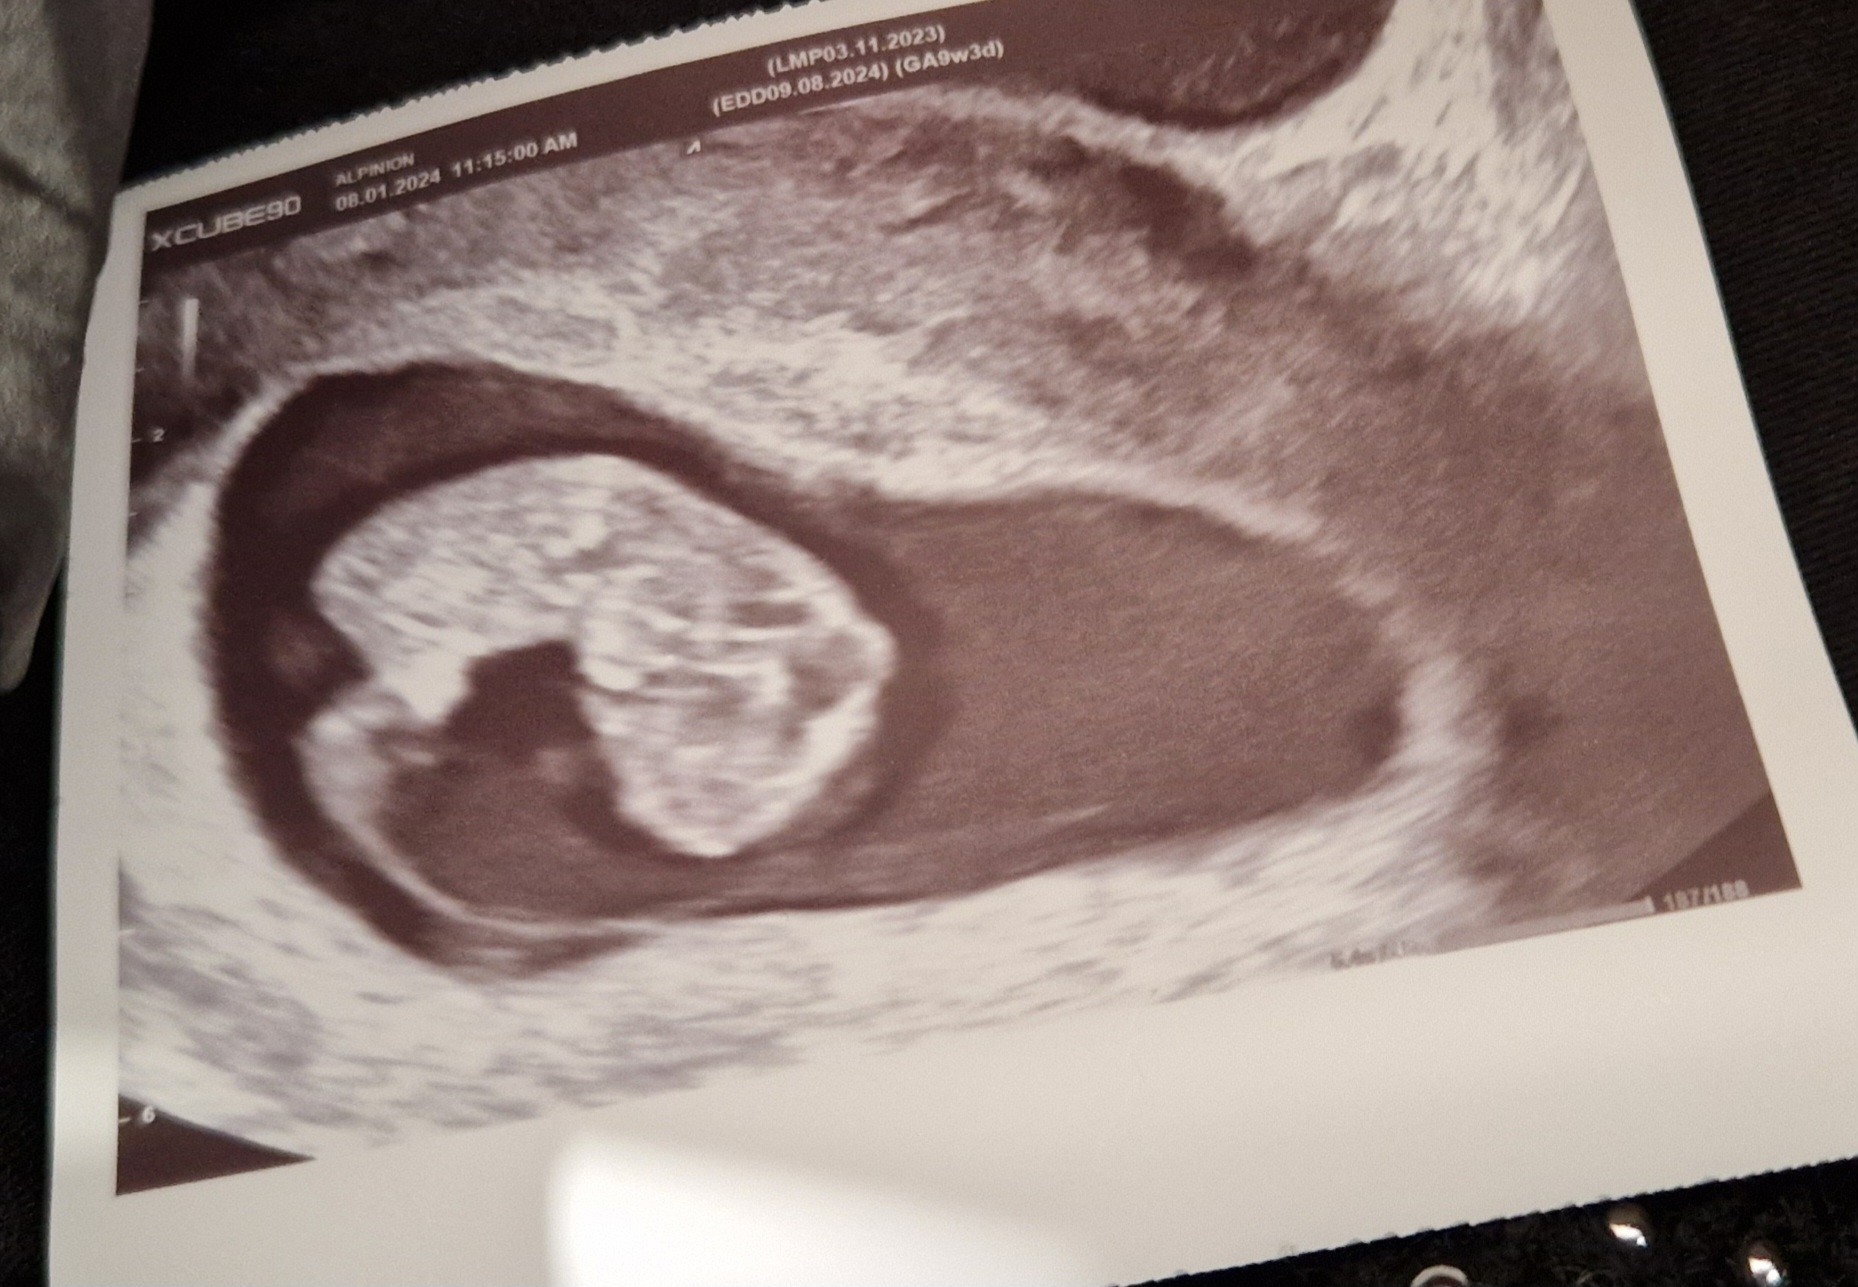

To lepiej niż w Austrii, bo tutaj te trzy duże USG są płatne

ubezpieczenie chyba tylko 5 wizyt z USG takim ogólnym pomiarem tętna refunduje. Albo nawet i nie tyle. No ale jak będzie trzeba to zapłacę.